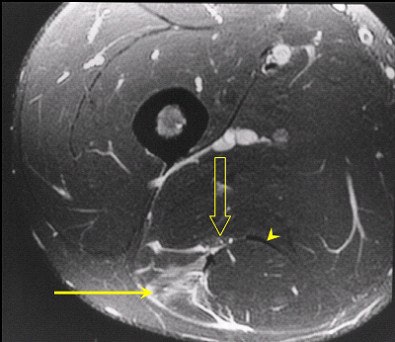

| Axial MR images through another patient demonstrates a tear of the belly of semitendinosus (arrow) with the tendon also noted (arrow head). Free fluid around the muscle comes into contact with the sciatic nerve (open arrow) which accounted for the patients' clinical symptoms of radiculopathy. |

MRI also probably depicts fluid around the sciatic nerve more accurately, which may account for neural tension and radiculopathy following injury. This has been postulated to be a cause of recurrent injury following injury to the HMC, as well as a prolonged rehabilitation period.